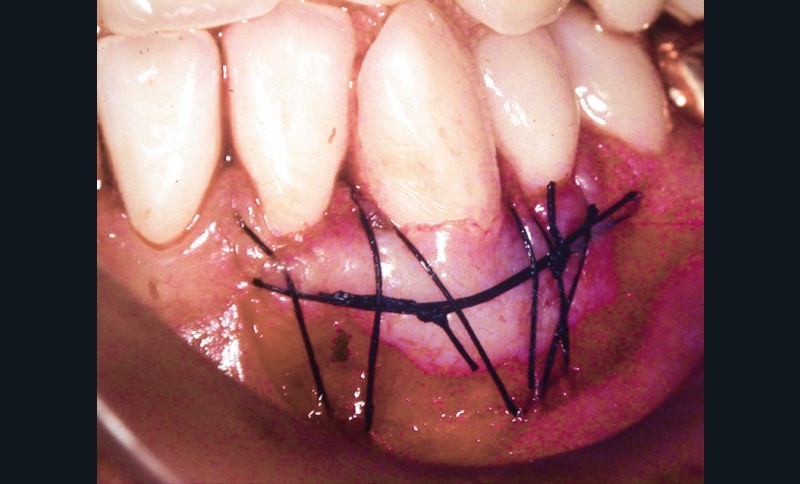

Une greffe épithélio-conjonctive est réalisée (fig. 4).

Positionnée plus coronairement que la précédente (fig. 5), elle permettra de recouvrir la récession et de recréer un lambeau de gencive attachée (fig. 6).